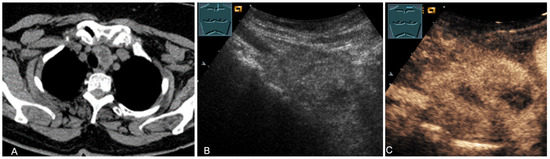

Figure 21.

A young patient with tumor formation in the anterior mediastinum on CT (provided by Prof. Dr. Andreas H. Mahnken, Marburg, Germany) (A), B-mode US (B), and CEUS (C), confirmed by biopsy as Hodgkin’s disease.

Figure 22.

A patient with tumor formation in the anterior mediastinum on CT (provided by Prof. Dr. Andreas H. Mahnken, Marburg, Germany) (A), B-mode US (B), and CEUS (C), confirmed by biopsy as diffuse large B-cell non-Hodgkin’s lymphoma.